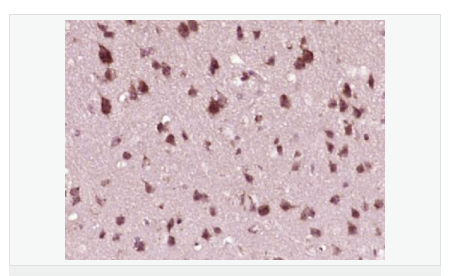

Rabbit anti-phospho-IRF3 (Ser386) Polyclonal antibody

英文名稱phospho-IRF3 (Ser386)

中文名稱磷酸化干擾素調(diào)節(jié)因子3抗體

別    名IRF3 (phospho S386); IRF3 (phospho Ser386); p-IRF3 (Ser386); p-IRF3 (S386); Interferon regulatory factor 3; IRF 3; IRF-3; IRF3; IRF3_HUMAN; MGC94729.

產(chǎn)品類型磷酸化抗體

研究領(lǐng)域腫瘤  細(xì)胞生物  細(xì)胞凋亡  轉(zhuǎn)錄調(diào)節(jié)因子  表觀遺傳學(xué)

抗體來(lái)源Rabbit

克隆類型Polyclonal

交叉反應(yīng)Human, Mouse,  (predicted: Rat, Dog, Pig, Cow, Rabbit, )

產(chǎn)品應(yīng)用WB=1:500-2000 ELISA=1:5000-10000 IHC-P=1:100-500 IHC-F=1:100-500 Flow-Cyt=1ug/test ICC=1:100-500 IF=1:50-200 (石蠟切片需做抗原修復(fù))

分 子 量47kDa

細(xì)胞定位細(xì)胞核 細(xì)胞漿

免 疫 原KLH conjugated synthesised phosphopeptide derived from human IRF3 around the phosphorylation site of Ser386:S(p-S)LE

產(chǎn)品介紹This gene encodes a member of the interferon regulatory transcription factor (IRF) family. The encoded protein is found in an inactive cytoplasmic form that upon serine/threonine phosphorylation forms a complex with CREBBP. This complex translocates to the nucleus and activates the transcription of interferons alpha and beta, as well as other interferon-induced genes. Alternatively spliced transcript variants encoding multiple isoforms have been observed for this gene. [provided by RefSeq, Nov 2011].

Key transcriptional regulator of type I interferon (IFN)-dependent immune responses and plays a critical role in the innate immune response against DNA and RNA viruses. Regulates the transcription of type I IFN genes (IFN-alpha and IFN-beta) and IFN-stimulated genes (ISG) by binding to an interferon-stimulated response element (ISRE) in their promoters. Acts as a more potent activator of the IFN-beta (IFNB) gene than the IFN-alpha (IFNA) gene and plays a critical role in both the early and late phases of the IFNA/B gene induction. Found in an inactive form in the cytoplasm of uninfected cells and following viral infection, double-stranded RNA (dsRNA), or toll-like receptor (TLR) signaling, becomes phosphorylated by IKBKE and TBK1 kinases. This induces a conformational change, leading to its dimerization and nuclear localization and association with CREB binding protein (CREBBP) to form dsRNA-activated factor 1 (DRAF1), a complex which activates the transcription of the type I IFN and ISG genes. Can activate distinct gene expression programs in macrophages and can induce significant apoptosis in primary macrophages.

Constitutively phosphorylated on many serines residues. C-terminal serine/threonine cluster is phosphorylated in response of induction by IKBKE and TBK1. Ser-385 and Ser-386 may be specifically phosphorylated in response to induction. An alternate model propose that the five serine/threonine residues between 396 and 405 are phosphorylated in response to a viral infection. Phosphorylation, and subsequent activation of IRF3 is inhibited by vaccinia virus protein E3.